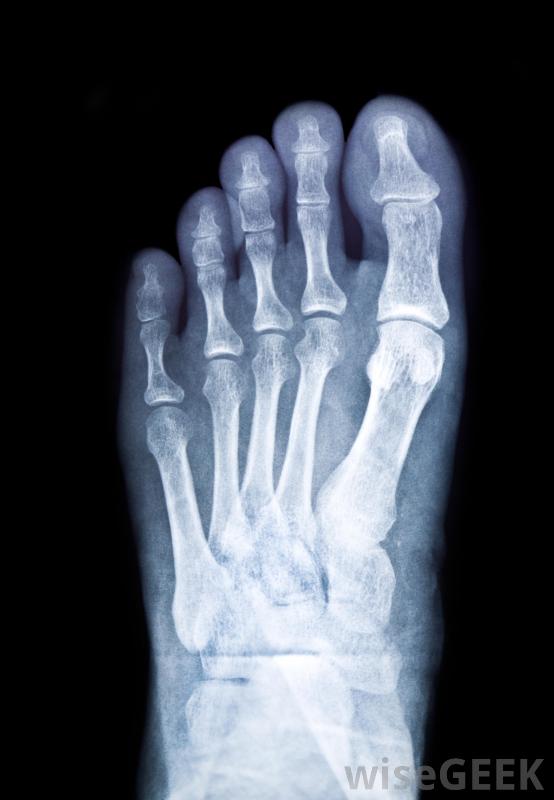

我怎么治療斷了的腳(Treat a Broken Foot)?

治療斷腳的第一步是脫下鞋子和襪子,抬起腳來。腳應該放在高于心臟的角度,以幫助減輕腫脹。你還應該在傷口上敷一層冰袋,但要注意不要直接放在皮膚上,通常在使用冰塊前最好在腳上墊上毛巾,當腳抬高并有冰袋后,可以用夾板將其包裹在一個大枕頭或毯子中醫生通常會對骨折的腳進行x光檢查,以確定損傷的嚴重程度。除了治療骨折的基本步驟外,注意腳部或身體其他可能受傷的部位出血也是個好主意,只要出血不嚴重,一些輕微的壓力和繃帶可能有助于止血。在敷繃帶之前,一定要先清洗傷口,這樣你就可以看到傷口有多嚴重。抬起腳來減輕腫脹,還有助于阻止腳部出血治療骨折的腳通常需要石膏。在骨折的腳用夾板固定,止血或減少后,您需要要么打電話給醫務人員,要么把傷者送到急診室如果傷勢嚴重,你可能需要在做任何其他事情之前叫救護車來確保救援盡快到達。在大多數情況下,在去急診室的途中或在你等救護車的時候,給傷者一些非處方止痛藥是可以的。如果傷者大量出血,避免服用阿司匹林,因為這會導致血液變薄,從而導致更嚴重的出血抬起斷了的腳直到能見到醫生,這一點很重要。醫生通常會做一些X光片來確定骨折的嚴重程度大多數情況下,腳會被放置在石膏里,病人需要使用拐杖來減輕腳上的重量,直到它愈合為止。骨折的腳愈合所需的時間通常取決于它的骨折程度。醫生也可能會開一些止痛處方藥。醫生可能會進行隨訪到了脫模的時候,他或她就可以確定它已經正確地愈合了。應該給骨折的腳敷上冰袋腳骨折的患者需要使用拐杖將重量從腳上移開,直到痊愈治療斷腳的第一步是抬起腳。